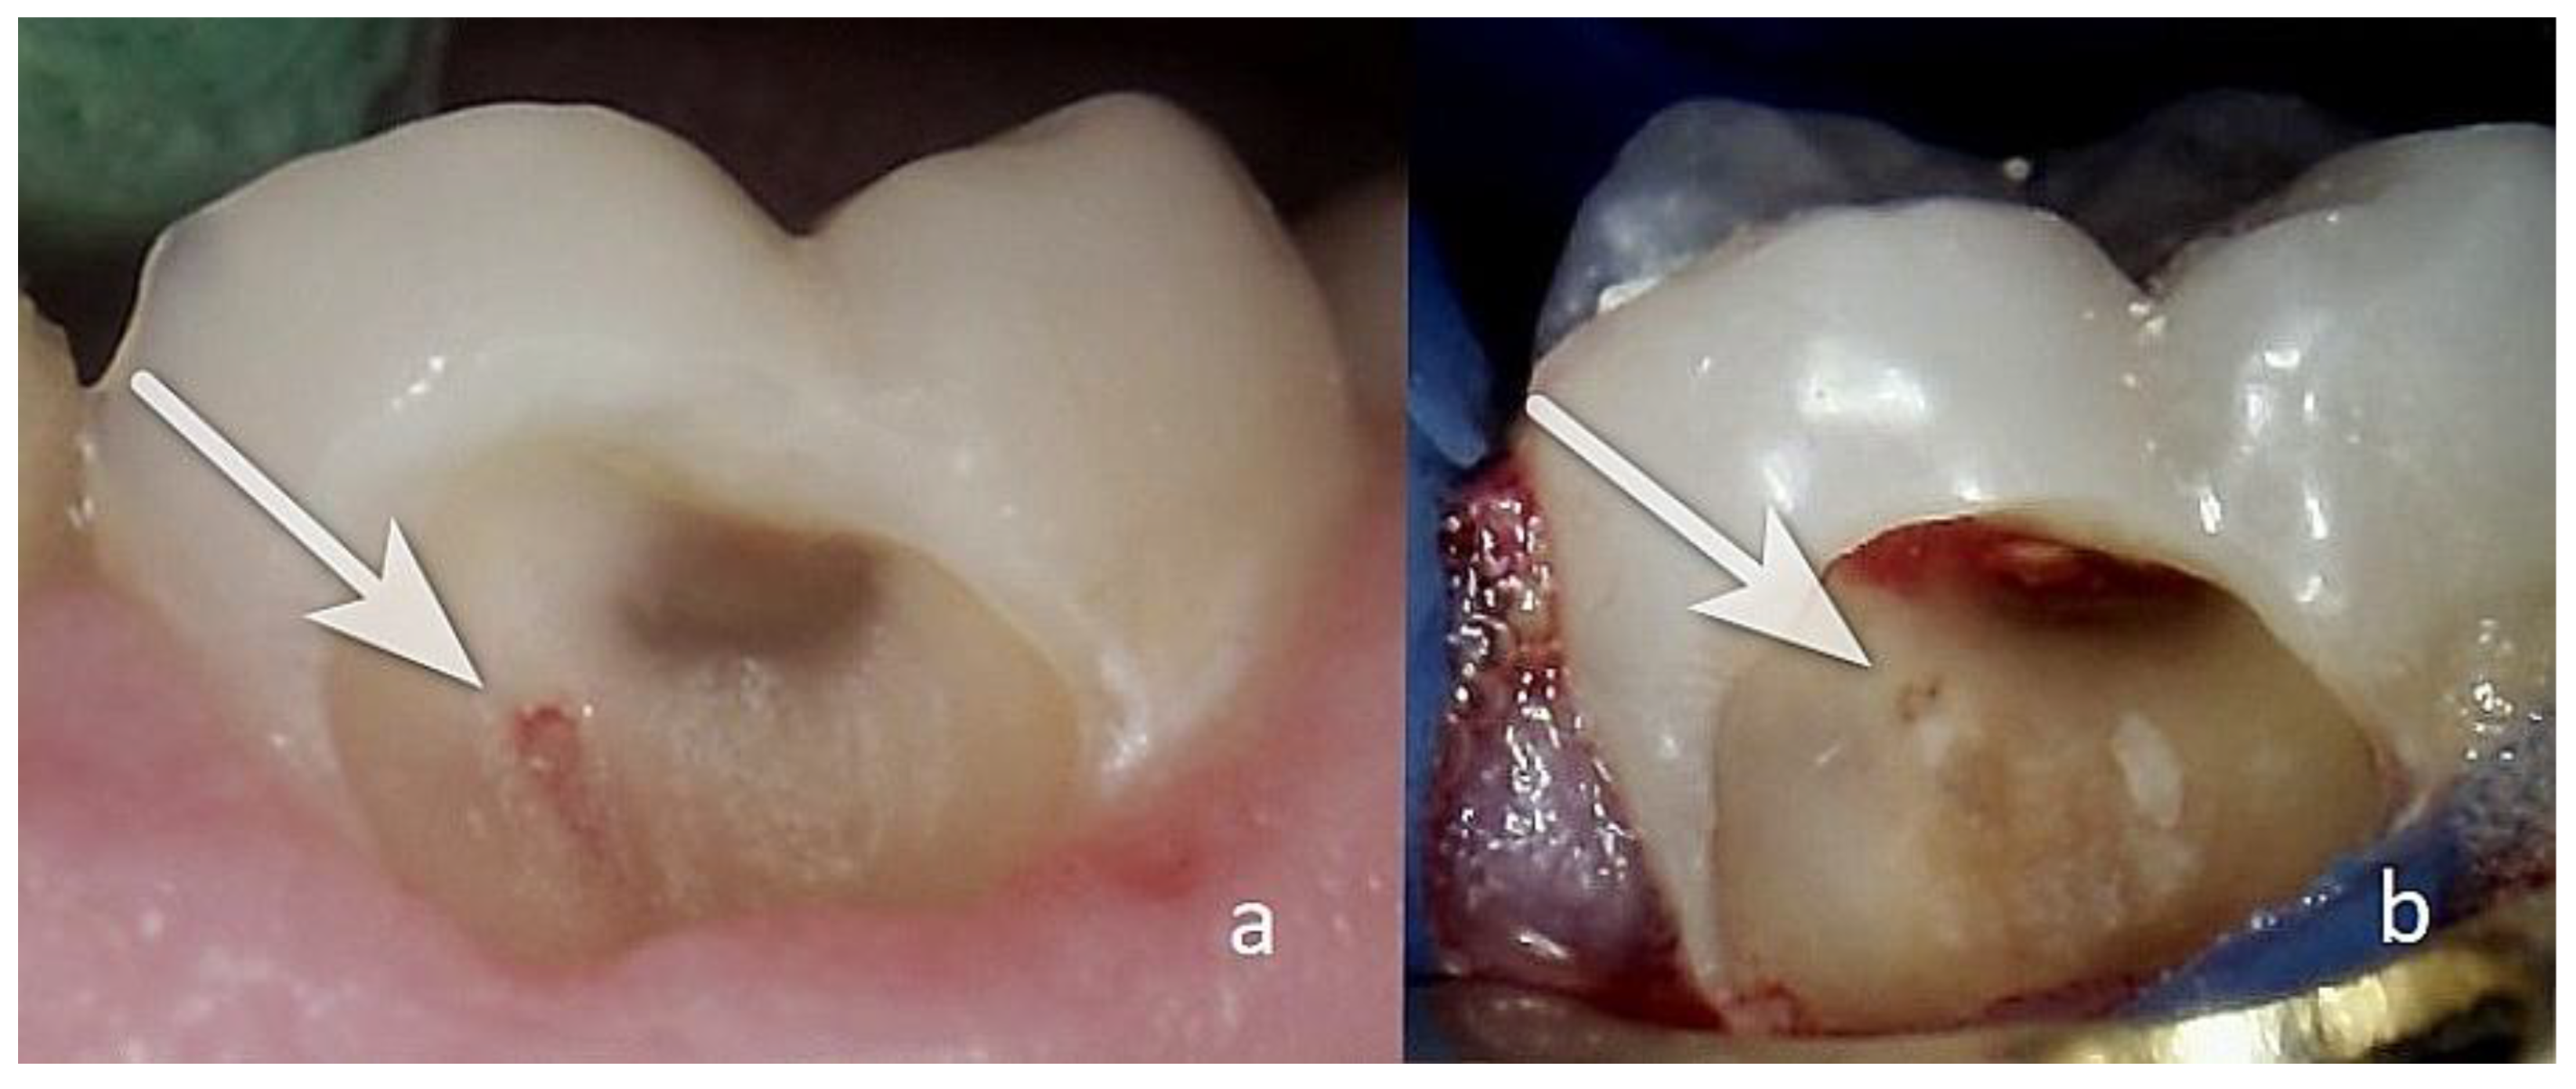

Colour. It is crucial to meticulously assess the colour of the exposed pulp—pink, light red, dark red, livid (Figure 6(d)), or black (Figure 6(a)). The most favourable range is from pink to red (Figure 7), underscoring the importance of this assessment.

The pulp tissue may be at the level, below the level (Figure 6a,c), or above the level of the surrounding dentin (Figure 6(d)). It’s important that the pulp communication is at the level of the surrounding dentin (Figure 7), as this facilitates cleaning and minimizes the risk of infection.

The colour of the surrounding dentin is also important. The intense redness of the dentin, as seen in Figure 6(b),(c), is a sign of hyperaemia of the dental pulp, and such cases are not suitable for direct pulp capping.

As shown in Figure 6(d), the dentin is dark in some areas. The pulp communication itself, measuring <1.5 mm, is dark red and is covered with a yellowish tissue fluid, likely indicative of inflammation. Dentin pieces can be seen deep within the pulp tissue. This is unfavourable, as the dentin in the pulp wound is probably infected and will adversely affect the healing process, making this case unsuitable for direct pulp capping.

Figure 6. View of a pulp injury not suitable for direct pulp capping. In all these cases, the surrounding dentin is clean and smooth. (a) clinical case N27. Upper first molar: occlusal view. The three pulp horns are visible. The dentin tissue between them is healthy. The communication with the dental pulp is marked in red with white arrows; it is homogeneous but significantly below the level of the surrounding dentin. The communication with the dental pulp mesio-buccally is indicated with a black arrow, showing possible signs of tissue necrosis. (b) clinical case N26. Lower first molar: distal. A white arrow indicates communication with the dental pulp towards the distal vestibular pulp horn—red with a homogeneous consistency, at the level of the surrounding dentin. Strong translucency of the dental pulp is marked with black arrows in red colour, almost throughout the entire axial wall, likely signs of increased hyperaemia of the tissue. (c) clinical case N22. Upper second premolar. In the area of the vestibular pulp horn, communication with the dental pulp is observed. The communication, indicated by a white arrow, is approximately 1 mm in size and is located below the level of the dentin. A black arrow points to a depression towards the dental pulp, below the level of the surrounding dentin, in which there are dentin flakes. The available pieces of pulp tissue are likely infected. Therefore, it is an unfavourable sign. (d) clinical case N6. Lower first molar: occlusal. The communication with the dental pulp is around 1–1.5 mm with a dark red colour and is covered with a tissue fluid of a yellowish colour with dentin fragments in the wound(white arrow). In some areas of the dentin, dark spots are visible.

Figure 7. (a) Case 1; (b) case 2. Appearance of a pulp injury suitable for direct pulp capping(white arrowa), with healthy dentin surrounding it. The surface of the communication with the pulp is at the level of the surrounding dentin; the pulp injury is flat with a reddish colour, homogeneous, and without signs of necrosis [16].